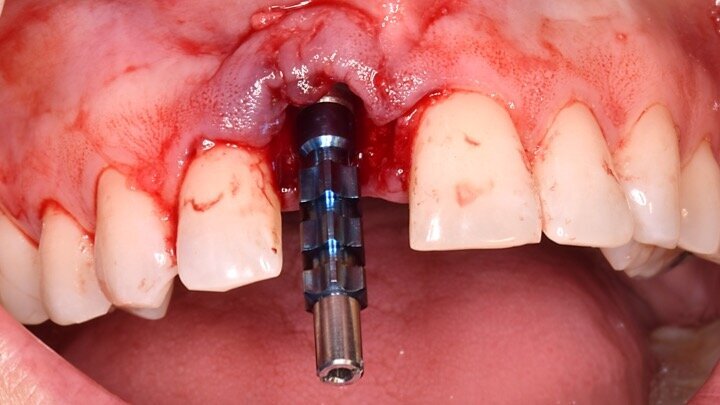

Figura 7. Implante de conexión interna insertado 2 mm por debajo de la cresta ósea, independientemente del defecto existente y a 55 Nw. Al no existir margen vestibular, tomamos como referencia los dos picos óseos de las papilas y entre ellos trazamos una línea imaginaria que los una enterrando el hombro unos 2 ó 3 mm por debajo de ella.

Figura 8. Esperamos a que la superficie del implante esté siempre cubierta por un coágulo de sangre antes de adaptar el material encima de éste.